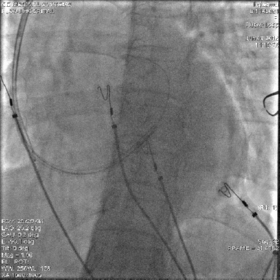

最终影像

AP

LAO

RAO